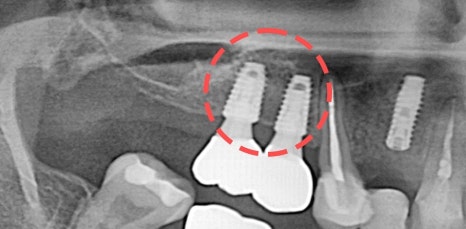

특히 위쪽 어금니 쪽이 상실 되어 임플란트 시술을 진행해야 하는데 잇몸 뼈가 부족한 상태라면 추가적으로 상악동거상술을 함께 진행해야 했어요. 상악동이란 코 양옆에 위치하고 있으며 뼈 속에 비어 있는 공기 주머니로 두개골의 무게를 줄여주는 곳이었어요. 상악동은 아주 얇은 막으로 둘러 쌓여 있으며 상악 쪽의 잇몸 뼈가 부족한 상태로 임플란트를 식립 하게 된다면 상악동 막이 찢어지거나 천공이 생길 수 있었어요.

상악동에 천공이 생기게 된다면 염증으로 인해 부작용이 생길 수 있었어요. 그렇기 때문에 환자 개개인마다 크기와 위치가 모두 다른 상악동의 위치와 잇몸 뼈의 두께를 정확히 파악하는 것이 중요했어요. 정밀 검사 후 임플란트를 식립 하기에 잇몸 뼈의 양이 부족하다는 진단이 나오게 된다면 얇은 상악동 막을 들어올려 준 후 필요한만큼의 뼈 이식을 진행해 주는 방법이 상악동거상술이었어요.

신논현역임플란트에서 말하는 상악동거상술은 치조정접근법과 측방접근법인 두가지 방법으로 진행할 수 있었어요. 남아 있는 잇몸 뼈의 양에 따라 이식 해야 하는 양이 달라지고 그로 인해 상악동에 접근 하는 방법을 기준으로 두가지 방법은 나눠 지고 있었어요. 먼저 치조정접근법은 잇몸 뼈가 4-8mm 정도 확보 되었을 때 사용하는 방법으로 치아가 상실 된 위치의 잇몸에 작은 구멍을 뚫어 준 뒤 그 구멍을 통해 상악동 막을 들어 올린 후 뼈 이식을 진행하는 방법이었어요.

작은 절개 범위와 뼈 이식 양이 많지 않기 때문에 수술 시간이 짧고 통증과 붓기도 적으며 회복 속도 또한 측방접근법에 비해 빠른 편이었어요. 반면 측방접근법은 잇몸 뼈가 4mm 이하로 많은 양의 잇몸 뼈를 이식 해야 할 때 필요한 방법이었어요. 잇몸 측면에서 큰 창 모양으로 절개 후 접근하는 방법으로 수술시간이 길고 붓기, 통증이 큰 편으로 회복 속도 또한 더딘 편이었어요.

하지만 시야 확보가 잘 되어 출혈과 돌발 상황에 대한 대처를 빨리 할 수 있어 안전하게 수술을 마무리 할 수 있다는 장점이 있었어요. 치조정접근법과 측방접근법 두가지 방법 중 어떠한 방법이 더 유리하고 안전하다고 할 수 없으며 치조골의 상태와 식립 해야 하는 임플란트의 개수, 상악동의 위치와 두께 등을 고려하여 환자분께 적합한 방법으로 상악동거상술을 진행 하는 것이 가장 안전하고 좋은 방법이라고 할 수 있었어요.